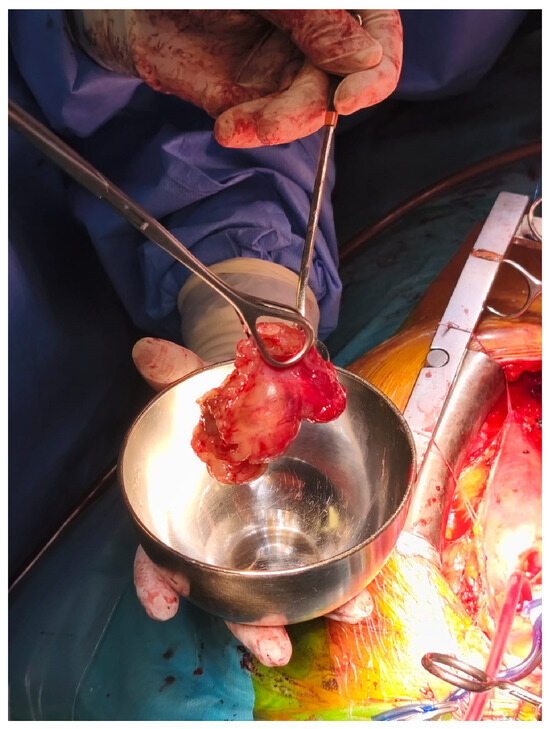

Due to the severity of the presentation and the unclear etiology, an urgent bedside transthoracic echocardiogram (TTE) was performed. This examination revealed a large, mobile, pedunculated mass measuring approximately 3.7 × 4.5 cm, located in the left atrium and attached to the interatrial septum at the level of the fossa ovalis. The mass was prolapsing through the mitral valve during diastole, causing significant dynamic obstruction of left ventricular inflow, with a mean transmitral gradient of 14 mmHg (Figure 1). This finding was consistent with severe functional mitral stenosis and provided a clear explanation for the patient’s acute pulmonary edema and hemodynamic instability. No transesophageal echocardiography was deemed necessary, as the transthoracic study provided sufficient diagnostic information to confirm the presence of the obstructive intracardiac mass and to guide urgent surgical decision-making.

Figure 1. TTE Showing Cardiac Mass During Systole (A) and Diastole (B).